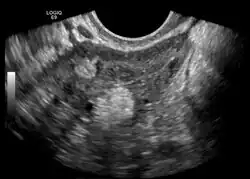

Dermoidzyste im transvaginalen Ultraschall

Die Dermoidzyste (früher auch Dermoidgeschwulst[1], im Volksmund auch fälschlich Zwilling[2] oder Zwillingsgewächs[3]) ist ein Hohlraum, der von Oberhautgewebe ausgekleidet ist. Die Dermoidzyste gehört zu den Teratomen.

Eine Dermoidzyste ist ein Keimzelltumor, ein reifes Teratom, das aus vollkommen verschiedenen Gewebearten besteht. Daher kann es innerhalb der Zyste zur Ausbildung von Gewebestrukturen wie Muskulatur, Knorpel, kleinen Knochen, Haaren und auch völlig ausgebildeten Zähnen kommen.